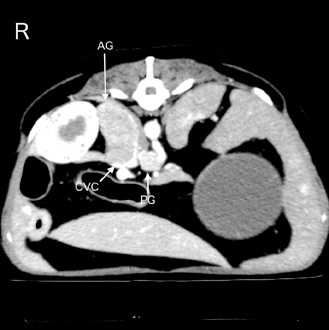

| Open Vet. J.. 2023; 13(11): 1465-1470 Open Veterinary Journal, (2023), Vol. 13(11): 1465–1470 Case Report Successful treatment of acute respiratory failure following hypertensive crisis in a dog with presumed pheochromocytoma or paragangliomaJun Tamura*, Shino Yoshida, Noriyuki Nagata, Genya Shimbo and Norihiko OyamaVeterinary Teaching Hospital, Faculty of Veterinary Medicine, Hokkaido University, Sapporo, Japan *Corresponding Author: Jun Tamura. Veterinary Teaching Hospital, Faculty of Veterinary Medicine, Hokkaido University, Sapporo, Japan. Email: j-tamura [at] vetmed.hokudai.ac.jp Submitted: 01/08/2023 Accepted: 04/10/2023 Published: 30/11/2023 © 2023 Open Veterinary Journal AbstractBackground: Acute respiratory failure has been reported as one of the manifestations of hypertensive crisis in pheochromocytoma in human medicine. In dogs, no reports have been described as acute respiratory failure following hypertensive crisis. Here, we report the clinical presentation, course, and treatment of acute respiratory failure following the hypertensive crisis in a dog with presumed pheochromocytoma or paraganglioma. Case Description: A 12-year-old neutered male toy poodle was referred for the diagnostic evaluation of a right adrenal gland mass. The dog suddenly exhibited severe dyspnea with abnormal hypertension (systolic blood pressure >200 mmHg) 15 minutes after recovery from the anesthesia for the computed tomography (CT) examination. Pulmonary CT and ultrasonography findings suggested acute onset of severe pulmonary edema. Pulmonary edema was treated with mechanical ventilation (pressure-support ventilation with continuous positive airway pressure) and negative fluid balance after the administration of furosemide. Weaning from mechanical ventilation was successful 24 hours after the onset of respiratory failure. Finally, the dog was discharged 3 days after weaning from ventilation without complications. Conclusion: This report outlines a case of acute respiratory failure following a hypertensive crisis requiring mechanical ventilatory management in a dog. The onset and progression of pulmonary edema were extremely rapid. However, improvement in pulmonary edema was also rapid. Hemodynamic stability, in addition to prompt diagnosis and aggressive therapeutic intervention, including mechanical ventilation, may have contributed to the good prognosis of pulmonary edema following hypertensive crisis in a dog, which we attribute to a catecholamine storm. Keywords: Acute respiratory failure, Catecholamine storm, Hypertensive crisis, Mechanical ventilation. IntroductionRespiratory failure occurs due to a disease or injury worsening the lungs’ ability to deliver oxygen or remove carbon dioxide (Summers et al., 2022). Symptoms of acute respiratory failure occur suddenly and can be life threatening (Summers et al., 2022). It requires immediate medication or oxygen supplementation. If oxygenation or ventilation impairment is severe, long-term mechanical ventilation is required. The outcomes of mechanical ventilation for canine respiratory diseases appear to be heavily determined by the underlying disease (Drobatz et al., 1995; Hopper et al., 2007; Edwards et al., 2014; Cagle et al, 2022; Herrería-Bustillo et al., 2022; Nemi et al., 2023). In humans, acute pulmonary edema is one of the manifestations of hypertensive crisis in pheochromocytoma (Ng et al., 2023). It can be either cardiogenic or noncardiogenic (Ng et al., 2023). In dogs, a previous review article described pulmonary edema as a complication of hypertensive crisis in pheochromocytoma (Galac and Korpershoek, 2017). However, the onset and treatment of acute respiratory failure following hypertensive crisis in dogs have not been reported previously. This case describes the clinical presentation, course, and successful treatment of acute respiratory failure following a hypertensive crisis, possibly due to a catecholamine storm induced by a presumed pheochromocytoma or paraganglioma in a dog. Case DetailsA 12-year-old neutered male toy poodle, weighing 8.6 kg with a body condition score of 7 out of 9, was referred to the Internal Medicine Service at a veterinary teaching hospital for diagnostic evaluation of a right adrenal gland mass and cystic disease of the left kidney. The abnormalities were incidentally discovered during health screening at the referring hospital. The dog had been previously diagnosed with myxomatous mitral valve disease (MMVD) and biliary sludge. Oral administration of pimobendane, isosorbide dinitrate, theophylline, and ursodeoxycholic acid was initiated. Upon initial examination, the dog appeared healthy. The dog showed a normal heart rate (138 beats/minute) and blood pressure (systolic, mean, and diastolic blood pressures were 141, 115, and 103 mmHg, respectively) measured using an oscillometric device (Vet20; Sun Tech Medical Inc., Morrisville, NC). In addition, a grade Ⅲ/Ⅵ systolic murmur was identified. As the patient was panting, the respiratory rate (RR) could not be obtained. The complete blood count and biochemistry panel are shown in Table 1. Thoracic radiography revealed no abnormality. Transthoracic echocardiography revealed mitral regurgitation (peak velocity, 5.4 m/s) without left atrial dilatation (ratio of left atrial to aortic root diameter, 1.27). The mitral valve E-wave velocity was 0.9–1.0 m/s. Abdominal ultrasonography revealed an enlarged right adrenal gland (maximum width, 27 mm) and hyperechoic biliary sludge. It was difficult to determine vascular invasion of the enlarged adrenal gland. The urinary free normetanephrine to creatinine ratio measured by liquid chromatography tandem mass spectrometry at the Hokkaido University One Health Research Center in Sapporo, Japan, was high (259.05), suggesting pheochromocytoma (Sasaki et al., 2021). The plasma adrenocorticotropic hormone concentration and urinary cortisol creatinine ratio, measured by Fujifilm Corporation, Tokyo, Japan, are shown in Table 1. The dog was scheduled to undergo contrast-enhanced computed tomography (CT) with 300 mg iodine/ml iohexol (Omnipaque 300 injection; Daiichi Sankyo Co., Ltd., Tokyo, Japan) at 2 ml/kg for surgical planning of adrenalectomy 7 days after the initial examination at our hospital. A 22-gauge, 31-mm intravenous (IV) catheter (Supercath5; Medikit Co., Ltd., Tokyo, Japan) was placed in the cephalic vein, and general anesthesia was induced with IV administration of butorphanol (Vetorphal; Meiji Animal Health Co., Ltd., Tokyo, Japan) and propofol (PropoFlo; Zoetis Japan, Tokyo, Japan). After intubation, anesthesia was maintained using oxygen and isoflurane (Isoflu; Zoetis Japan, Tokyo, Japan). The electrocardiogram, pulse rate, RR, end-tidal carbon dioxide concentration, indirect mean arterial pressure (MAP), and percutaneous oxygen saturation (SpO2) were monitored using a multiparameter monitor (BSM-5192; Nihon Kohden Corporation, Tokyo, Japan). During the CT scan (Aquilion PRIME; Canon Medical Systems Corporation, Tochigi, Japan), intermittent positive pressure ventilation was maintained. The patient’s pulse rate ranged from 58 to 79 beats/minute, and MAP ranged from 68 to 79 mmHg during anesthesia. The time from the induction of anesthesia to extubation was 24 minutes, and recovery from anesthesia seemed to be very smooth. The dog was moved to the ward after spontaneous head lift was observed. CT scans showed a right adrenal gland mass invading the caudal vena cava (Fig. 1). In addition, the mass around the celiac and cranial mesenteric arteries was consistent with a previous report of paraganglioma (Gombert et al., 2022) (Fig. 1). The CT images of the lungs appeared normal, except for some bullae (Fig. 2A and B). Table 1. Laboratory findings on initial examination day.

Fig. 1. An abdominal CT image of the present case is shown. A right adrenal gland mass with invasion of the caudal vena cava is observed. In addition, a mass around the celiac and cranial mesenteric arteries, suggestive of a paraganglioma, is also detected. AG, adrenal gland mass; CVC, caudal vena cava; and PG, the mass suspecting a paraganglioma. The dog was anesthetized with IV propofol to effect with 0.2 mg/kg of IV butorphanol. After intubation, anesthesia was maintained with 1.5% isoflurane in oxygen (1 l/minute) delivered via a circular rebreathing system and an anesthetic machine with an out-of-circuit vaporizer (FO-20A; Acoma Medical Industry Co., Ltd., Tokyo, Japan). Spontaneous breathing was maintained, and an end-expiratory positive pressure of 5 cm H2O, adjusted by a manual semi-closed adjustable pressure-limiting valve, was applied for ventilatory support. In addition, 1 mg/kg IV of furosemide (Nichi-Iko Pharmaceutical Co., Ltd., Toyama, Japan) was administered to reduce pulmonary capillary osmotic pressure. Mild improvement was observed in pulmonary CT images 3 hours after the initiation of ventilatory support. During treatment, the pulse rate and MAP ranged from 108 to 140 beats/minute and 81 to 92 mmHg, respectively. The RR varied between 43 and 48 breaths/minute, and the end-tidal carbon dioxide concentration was between 32 and 35 mmHg. SpO2 was maintained between 96% and 100%. The partial pressures of arterial oxygen (PaO2) and carbon dioxide (PaCO2) analyzed using a blood gas analyzer (GEM-Premier 5000; IL Japan Co., Ltd., Tokyo, Japan) after the third CT scan, were 152 and 46 mmHg, respectively. The ratio of the PaO2 to the fraction of inspired oxygen (P/F ratio) was 152, and a diagnosis was made of severe oxygenation failure due to acute respiratory failure. After informed consent was obtained, a decision was made to implement more aggressive ventilatory management in the intensive care unit (ICU).